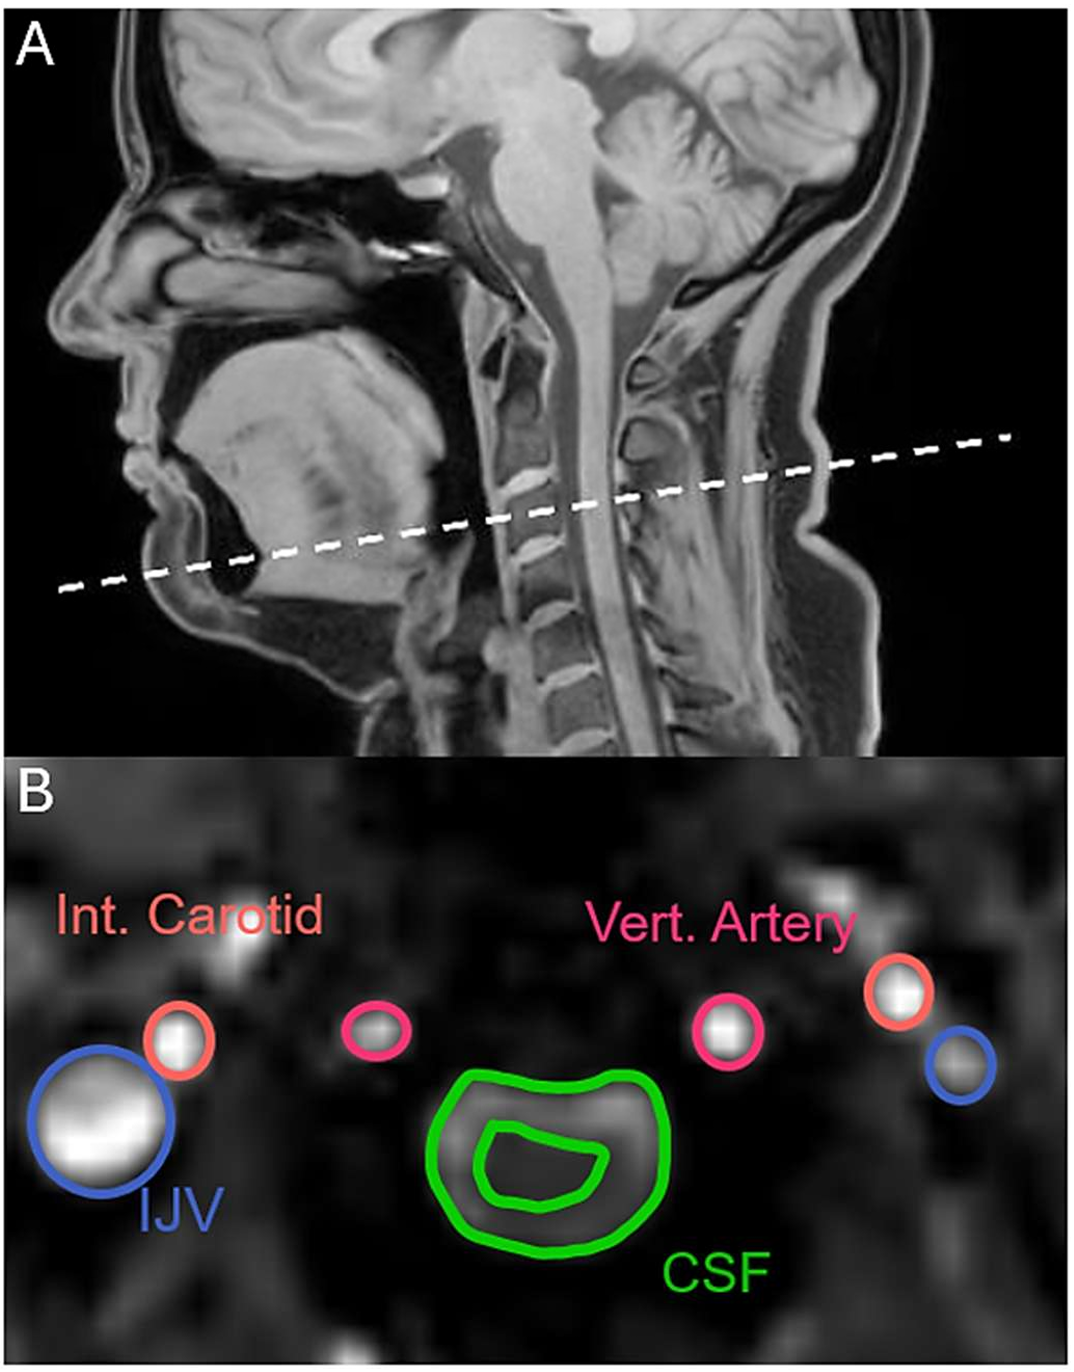

This research at the University of New South Wales, conducted with advanced MRI scanning technology, looked at how the brain migrates and moves during a yawn, as well as the amount of time it takes to migrate the CSF during the yawn. Adam Martinac, a neuroscientist at UNSW, and the researchers studied 22 healthy people and discovered some patterns that could explain the evolutionary pathway of yawning in many mammal species, including people.

“The yawn seems to be creating a flow of CSF away from the brain, whereas taking a deep breath causes a flow of CSF towards the brain,” Martinac claimed. “This was an unexpected finding for us.” Cerebrospinal fluid (CSF) surrounds and cushions the brain and spinal cord, as well as providing nutrients to the nervous system and assisting with the removal of waste. When someone takes a deep breath, their cerebrospinal fluid moves towards the brain. However, the fluid moves away from the brain while yawning.

The change in blood flow and pressure during yawning and taking a deep breath is also evident in the images. During yawning, there was an increase in blood flowing from the brain through the veins in the neck, creating space for fresh blood to enter the brain through the arteries.

Blood flow does not reverse direction when yawning, but during the initial phase of a yawn, the blood flow into the brain through the carotid arteries increases by 30%. Such an increase in blood flow into the brain during yawning indicates that yawning has a greater effect on circulation than just one factor.